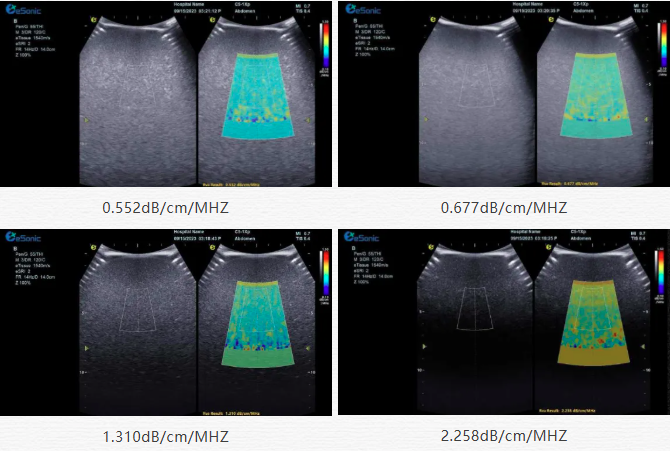

该技术基于声波在介质传播时的衰减,衰减由声吸收、反射、散射及波束扩散所致,声衰减系数(α,单位 dB/cm?MHz,与超声频率和传播距离成正比)可通过测定同频超声波在组织中的衰减程度,借回波信号分析预测声衰减系数或衰减率来评估组织特性。

声衰减定量成像(ATI)| 无创检测领域的革新之光(图2)

目前市面常用瞬时弹性成像或仿体参照法,存在适用性、准确性差及无衰减图局限。3377体育则采用准确度更高的 ALA 幅度损失衰减法,超声波深度传播时回波幅度渐降,其对数与深度有良好线性关系,声衰减量与传播衰减系数成函数关系,调节取样框大小位置可实时得样框内组织衰减系数,用于定量评估病变程度。